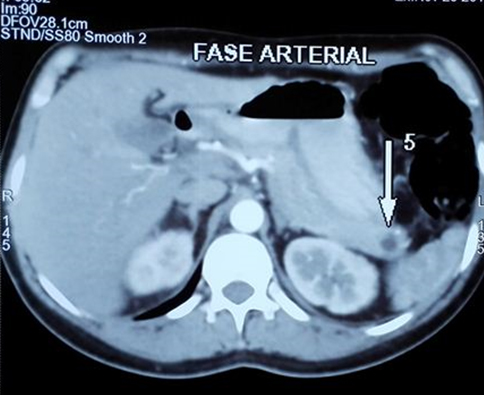

A 25-year-old African-American male was brought to Howard University Hospital as a trauma activation. The patient was described as being found with a facial laceration. At the scene, he was reported to be opening his eyes and moving all extremities when aroused. His car was noted to have multiple bullet holes in it. On primary survey, he was hemodynamically stable, his airway patent, breath sounds were clear bilaterally, and he had 2+ radial and dorsalis pedis pulses bilaterally. His GCS was 11; he was noted to be opening his eyes spontaneously, making incomprehensible sounds, and localizing to pain. On secondary survey, he had a 1 cm wound to the right supraorbital region with minimal bleeding. Other findings included vomitus around his mouth and decorticate posturing of his right upper extremity with normal movement of all other extremities. A non-contrast computed tomogram (CT) of the head demonstrated multiple hyperdense foreign bodies along a path from right to left involving the right supraorbital region, the right frontal lobe, and the left parietal lobe with involvement of the genu of the corpus callosum and left caudate. Scant blood was also noted in the lateral ventricular system and there were hemorrhagic changes in the left caudate nucleus as well as subarachnoid blood in the left sylvian fissure. A fracture of the inner and outer table of the skull with entry into the right frontal sinus was also identified as the bullet entry site.

D.L. returned to our Emergency Department 18 days post-discharge with headaches. He had full motor function of all extremities and was able to hold a conversation with minimal pauses between words. A CT scan of the head done revealed no interval changes compared to the post-operative scan. He was discharged home on oral analgesics and scheduled for a follow-up with the neurosurgeon. Over two subsequent follow-up visits at two and four weeks post-operatively, the patient had completely returned to normal neurologic and normal speech function. He remains on levetiracetam.